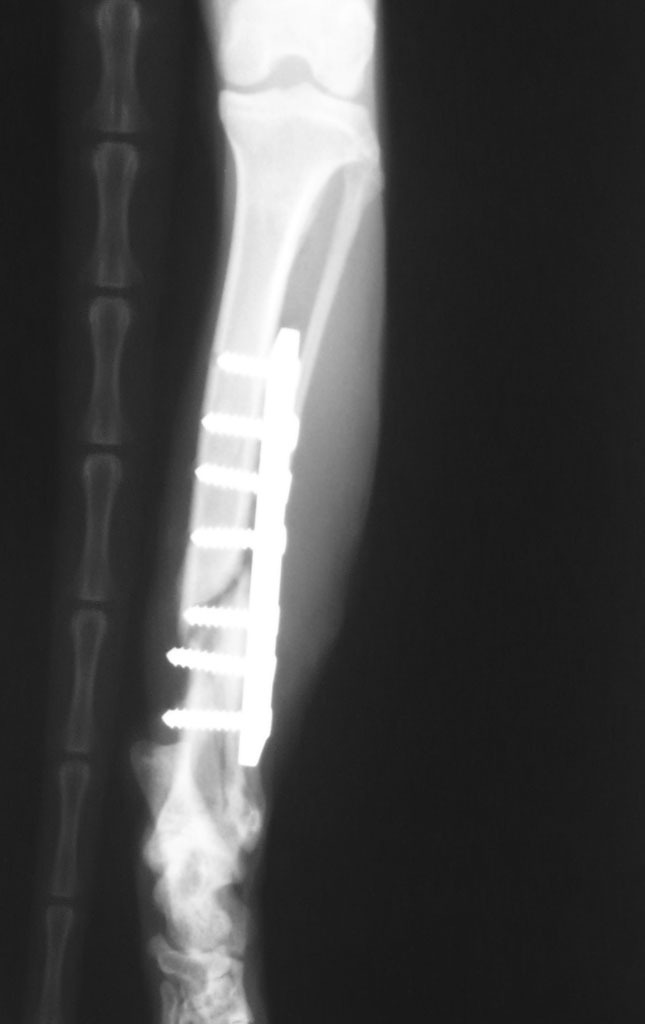

過兩天,抓到牠了,送到長沁醫院。麻醉完,張醫師打開牠的嘴一看,四顆犬齒全爛了,犬齒旁還有一個婁管(一個大洞),氣味非常不好聞,可見裡面已經嚴重發炎了,張醫師說,如果沒有及時處理,未來有可能會敗血症而死亡。之後照了x光,發現牠的後腿骨折了,需要馬上動手術處理。當天,晚上八點多我去醫院看牠,張醫師還在縫合傷口,手術時間頗長。

目前橘子貓骨折部分已完全癒合,已出院暫住中途家休養,待皮毛完全長出後,會原地野放照顧。